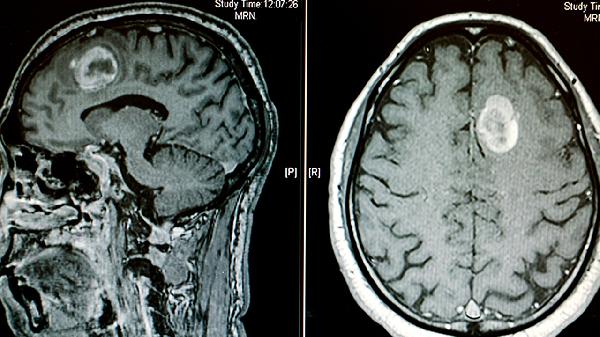

阿尔茨海默病、帕金森病等神经退行性疾病可引起脑实质萎缩,继发侧脑室被动性扩大。患者多伴有认知功能下降、运动障碍等表现。头部MRI显示脑沟增宽与脑室扩大并存,治疗以控制原发病为主。